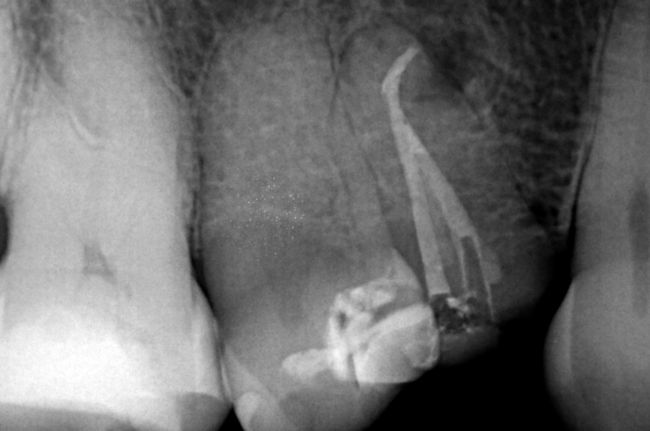

Dr. Alessandra Baasch, an Endodontics specialist, presents a clinical case instrumented with BlueShaper®️+ ApicalShaper®️.